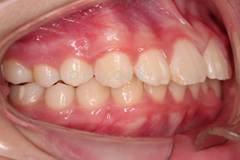

下面這個(gè)小患者就存在需早期矯正的問題。通過早期矯正,在不長(zhǎng)的時(shí)間內(nèi)就達(dá)到極為明顯的療效。她的情況如果等到牙齒替換完畢后再解決,矯治的難度則會(huì)非常大。

早期矯正之前